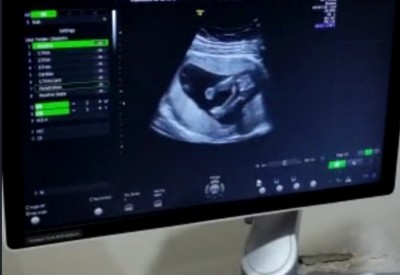

Cinsiyeti nedir tahmin

image

Edebilecek olan var mi :)

Doktor ne dedi. Erkek sanki canım

Doktor 15 . haftada cok erkege adapte olmayin demisti ama tabi yaniladabilir

Ahah çok tatlı yaa ayaklarini havaya kaldırmış kizz bncee☺️☺️❤️